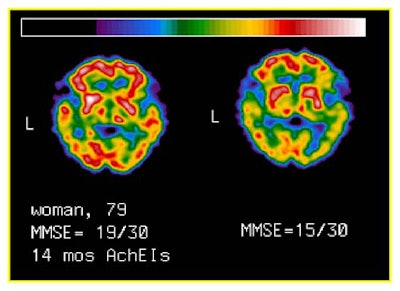

"Our patient population ... all had mild to moderate Alzheimer's disease, with (Folstein Mini Mental State Examination) MMSE scores higher than 14," Mariani said.

The patients, 15 women and 4 men aged 73.5 years (+/- 6.4 years) underwent clinical examination, neuropsychologic evaluation, and brain perfusion before therapy. The evaluations were repeated after approximately one year (10.6 months +/- 2.9 mo.) of continuous treatment with 5/mg/day of donepezil.

The results were based on changes in MMSE scores following therapy, Mariani said. The patients were divided into 11 "responders," whose MMSE scores changed from 0.18 +/- 1.6 (range -1 to +2). Their ages were 78 +/- 6 years, and their baseline MMSE scores were 19.6 +/- 3.9.

There were 8 "nonresponders," whose MMSE scores changed -4.38 +/- 1.3 (range -1 to +2). Their ages were 73 +/- 6 years, and their baseline MMSE scores were 19.6 +/- 3.8.

For example, there was a trend toward increased brain perfusion in responders, especially in the left parieto-temporal ROI. However, following (Bonferroni’s) adjustment for multiple comparisons, the increase did not reach statistical significance. No pattern of changes in brain perfusion was detected in nonresponders.

The responders showed a significant correlation between baseline MMSE scores and percentage rCBF changes in all ROIs, (R=0.47 to 0.7; P=0.05 to 0.01). The responders also showed significant correlation between the change in MMSE scores and rCBF percentage changes in all ROIs (R=0.61 to 0.8l; P=0.02 to 0.001), with the highest correlation in frontal ROIs.

"The message is that the patients with higher MMSE variations [following therapy] had milder [baseline] disease, at least in this particular case," Mariani said. "The second correlation is between the changes in MMSE scores and the change in cerebral perfusion" in the left parieto-temporal lobes. It may be that acetylcholinesterase inhibitor therapy is most effective in the better-preserved frontal areas of patients with mild AD, he said.